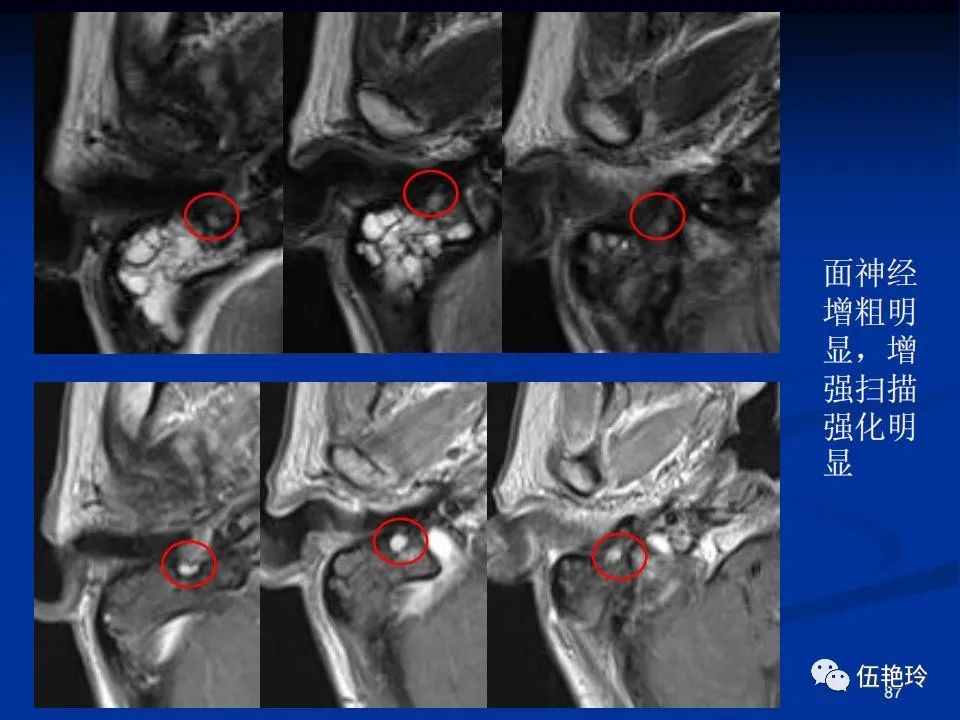

耳与面神经的解剖